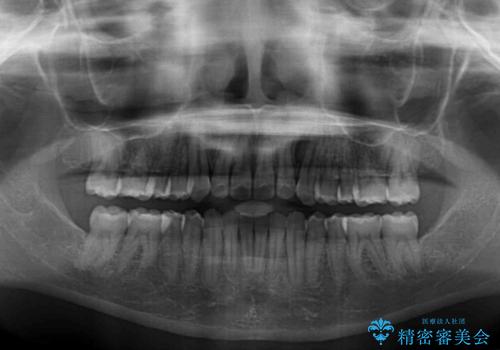

- 前歯のデコボコを気にして来院された患者様です。

上顎右側犬歯が八重歯になっており、それによって奥歯が前方に移動しているため、右側の咬み合わせの改善が必要と判断されました。

より治療を速やかに行うため、上顎右側にアンカースクリューを使用し、目標としていた1年半ほどで治療を終えることができました。